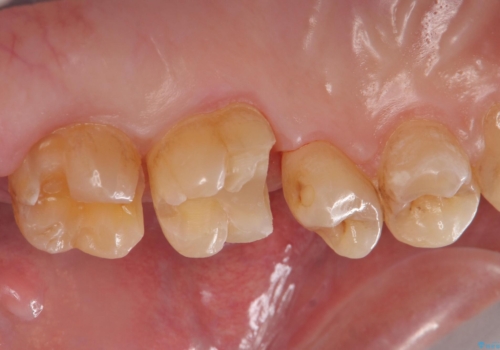

- 歯が欠けたとのことで来院された患者様です。

1本はゴールドアンレー、もう1本はセラミックインレーで修復します。

患者様の咬む力や削るべき歯の量によって、使用する材料を決めております。